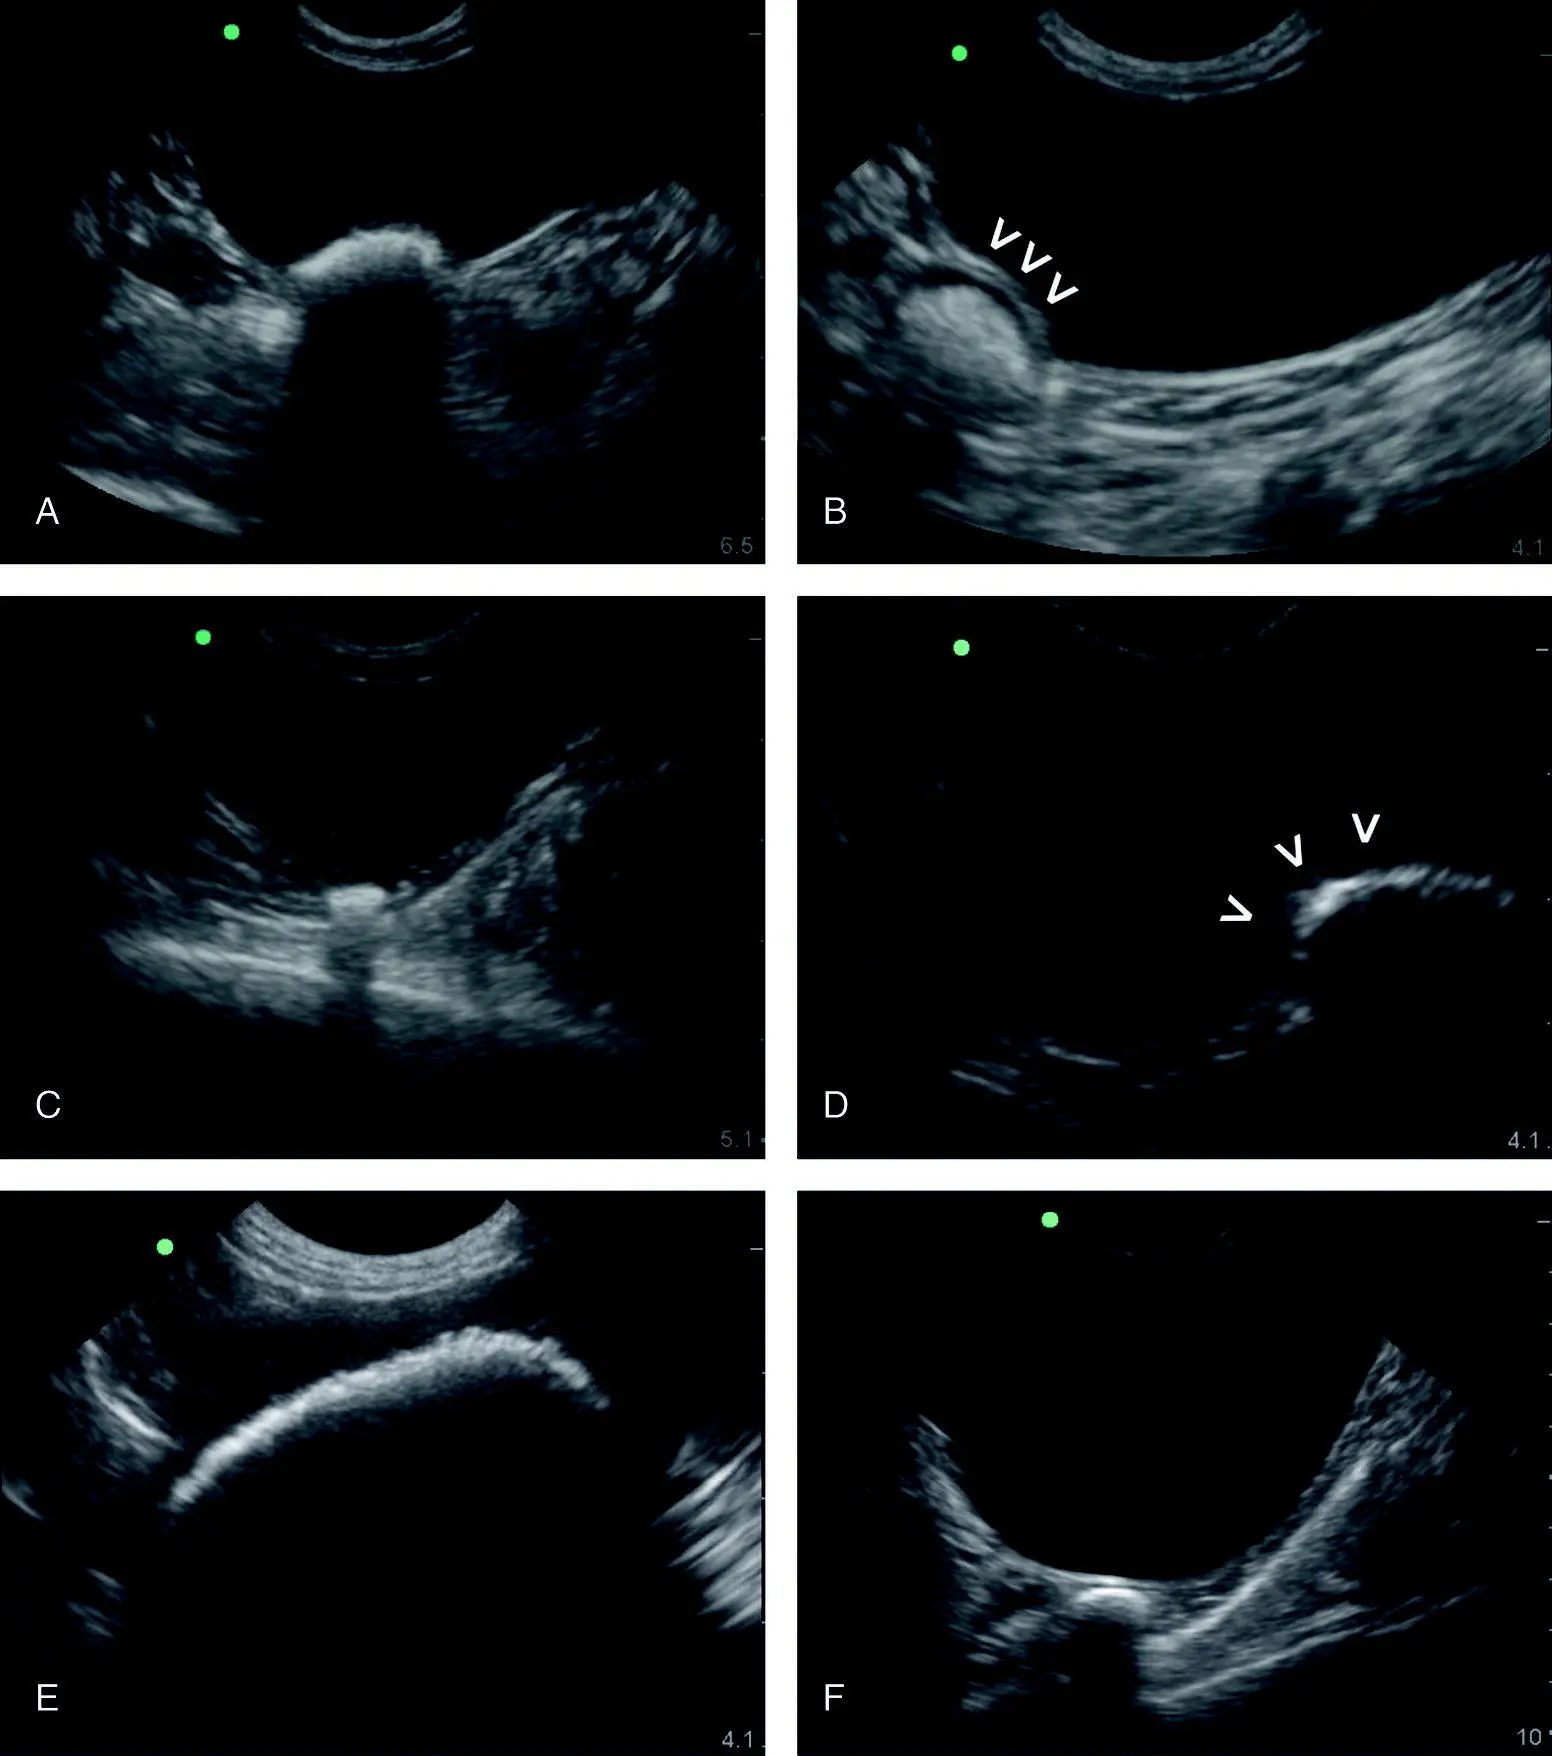

Figure 6.28. Various abnormal intraluminal urinary bladder findings. (A) An irregular urinary bladder wall in its apical region suggestive of chronic cystitis. (B) A soft tissue mass in the trigone region of the urinary bladder of an older female dog that was hit by a car (blunt trauma). The condition was captured and the dog diagnosed with a transitional cell carcinoma that lived with treatment for another 11 months. Color flow Doppler could be additionally applied to evaluate for blood flow (not shown). (C) Bladder calculi in a diabetic being admitted for hospitalized care. (D) A large thrombus in an older male bluntly traumatized dog. Color flow Doppler was helpful for documenting absent flow.

Source: Reproduced with permission of Dr Gregory Lisciandro, Hill Country Veterinary Specialists and FASTVet.com, Spicewood, TX.